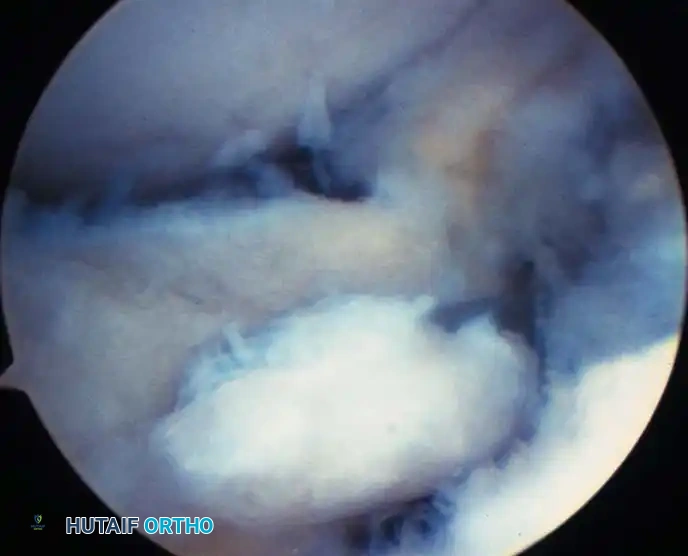

Arthroscopic view of the anterolateral gutter demonstrating synovial hypertrophy and soft-tissue impingement.

Arthroscopic visualization of an osteochondral defect (OCD) on the medial talar dome.

Arthroscopic view of the posterior gutter, a common hiding place for intra-articular loose bodies.

Further visualization of the posterior compartment structures, including the transverse ligament.